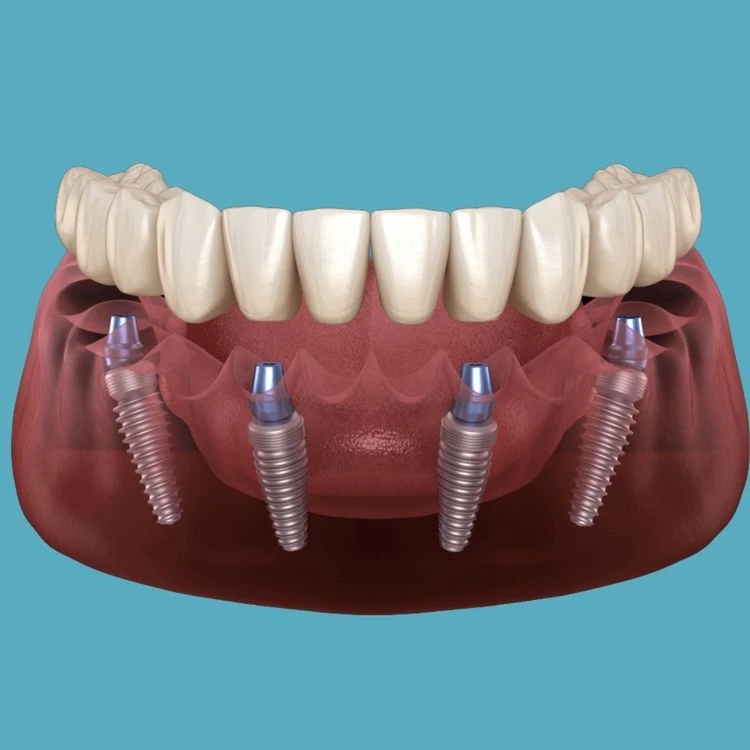

All-on-4 implant tedavisi, tüm dişlerinizi tek seans içerisinde çıkartılıp yerine 4 adet implant üzerine sabitlenen bir köprü ile değiştirmektir. Bu tedavi yöntemi, diş eksiklikleri olan kişilere daha hızlı ve daha kolay bir diş restorasyonu sağlar.

All-on-4 implant tedavisi, bir cerrahi işlemle yapılır. Tedavi sırasında, öncelikle diş etleri kaldırılır ve dişler çekilir. Sonrasında, implantlar çene kemiğine yerleştirilir ve geçici bir köprü takılır. Yerleştirilen implantlar iyileşme sürecinde kemikle kaynaşır ve kalıcı köprü yerleştirilir.